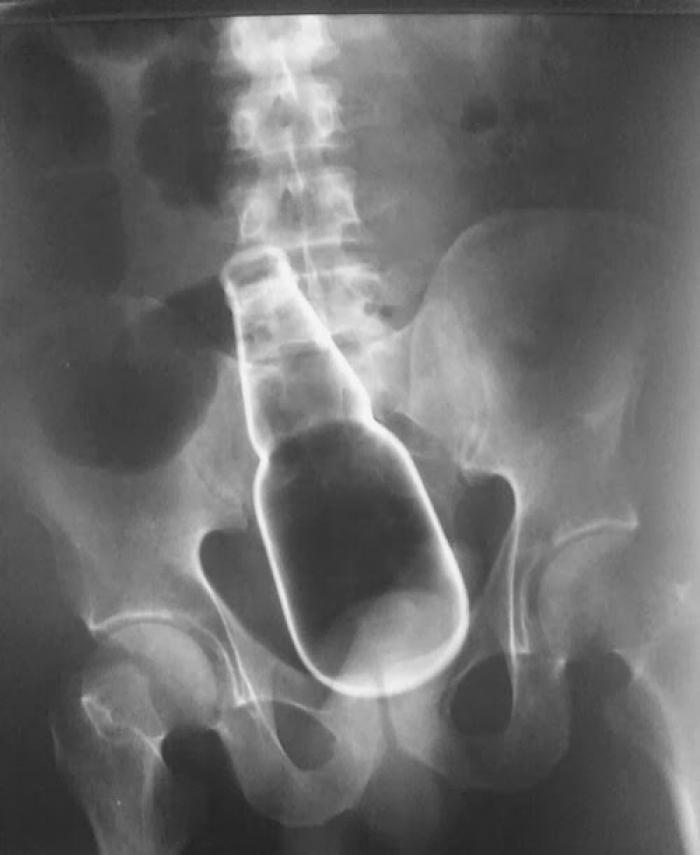

Razele X ne dovedesc că oamenii "pierd" adesea o mulțime de lucruri în propriul corp.